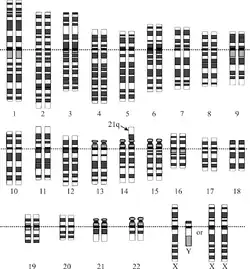

Translocación

Código CIE-10: Q90.2

Después de la trisomía libre, la causa más frecuente de aparición del exceso de material genético es la translocación. En esta variante el cromosoma 21 extra (o un fragmento de él) se encuentra «pegado» a otro cromosoma (frecuentemente a uno de los dos cromosomas del par 14), por lo cual el recuento genético arroja una cifra de 46 cromosomas en cada célula. En este caso no existe un problema con la disyunción cromosómica, pero uno de ellos porta un fragmento «extra» con los genes del cromosoma «translocado». A efectos de información genética sigue tratándose de una trisomía 21 ya que se duplica la dotación genética de ese cromosoma.

La frecuencia de esta variante es aproximadamente de un 3 %[25] de todos los SD y su importancia estriba en la necesidad de hacer un estudio genético a los progenitores para comprobar si uno de ellos era portador sin saberlo de la translocación, o si esta se produjo por primera vez en el embrión. (Existen portadores «sanos» de translocaciones en los que se recuentan 45 cromosomas, uno de los cuales está translocado, o pegado, a otro).

Mosaicismo

Código CIE-10: Q90.1

La forma menos frecuente de trisomía 21 es la denominada «mosaico» (en torno al 2 %[26] de los casos). Esta mutación se produce tras la concepción, por lo que la trisomía no está presente en todas las células del individuo con SD, sino solo en aquellas que proceden de la primera célula mutada. El porcentaje de células afectadas puede abarcar desde unas pocas a casi todas, según el momento en que se haya producido la segregación anómala de los cromosomas homólogos.